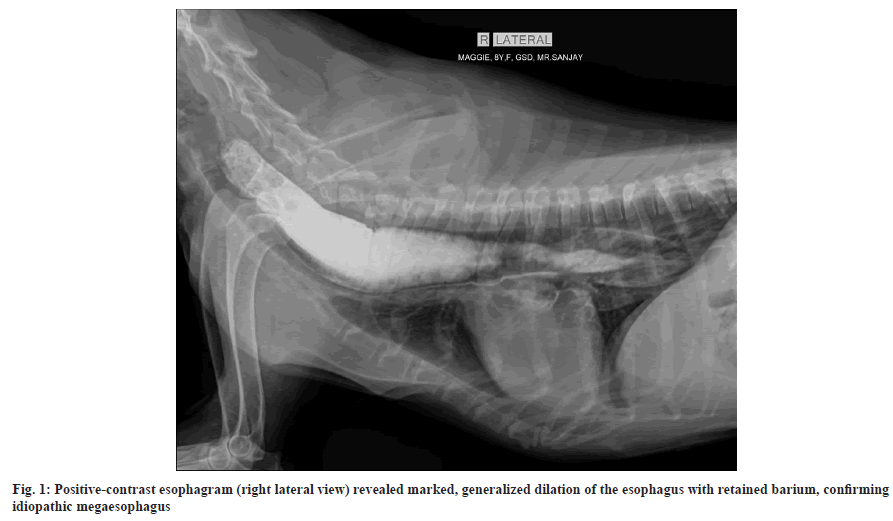

An 8 y-old, 25 kg, female German shepherd dog was presented with frequent regurgitation, intermittent cough, and suspected esophagitis. Thoracic radiography and a positive-contrast esophagram (right lateral view) demonstrated marked, generalized esophageal dilation with retained barium, consistent with idiopathic megaesophagus (fig. 1). Initial management included dietary modification with a soft, slurry diet and acid suppression using omeprazole (1 mg/kg orally every 12 h). After 2 w of therapy, regurgitation frequency remained high and clinical improvement was minimal.